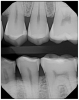

Attrition (Table 4) is the normal loss of tooth substance that results from friction by physiologic forces.7 Dental attrition is caused by tooth-to-tooth contact, resulting in loss of tooth tissue, usually starting at the incisal or occlusal surfaces. Clinical crown damage of the teeth can significantly thin the enamel structure, thus exposing the underlying structure called dentin (Figure 1). Dentin is softer and darker, increasing the risks of sensitivity, decay and discoloration. The etiology of dental attrition is multifactorial, with the most common cause being bruxism.

Figure 1. Attrition exposing dentin on tooth #25.

Figure 1